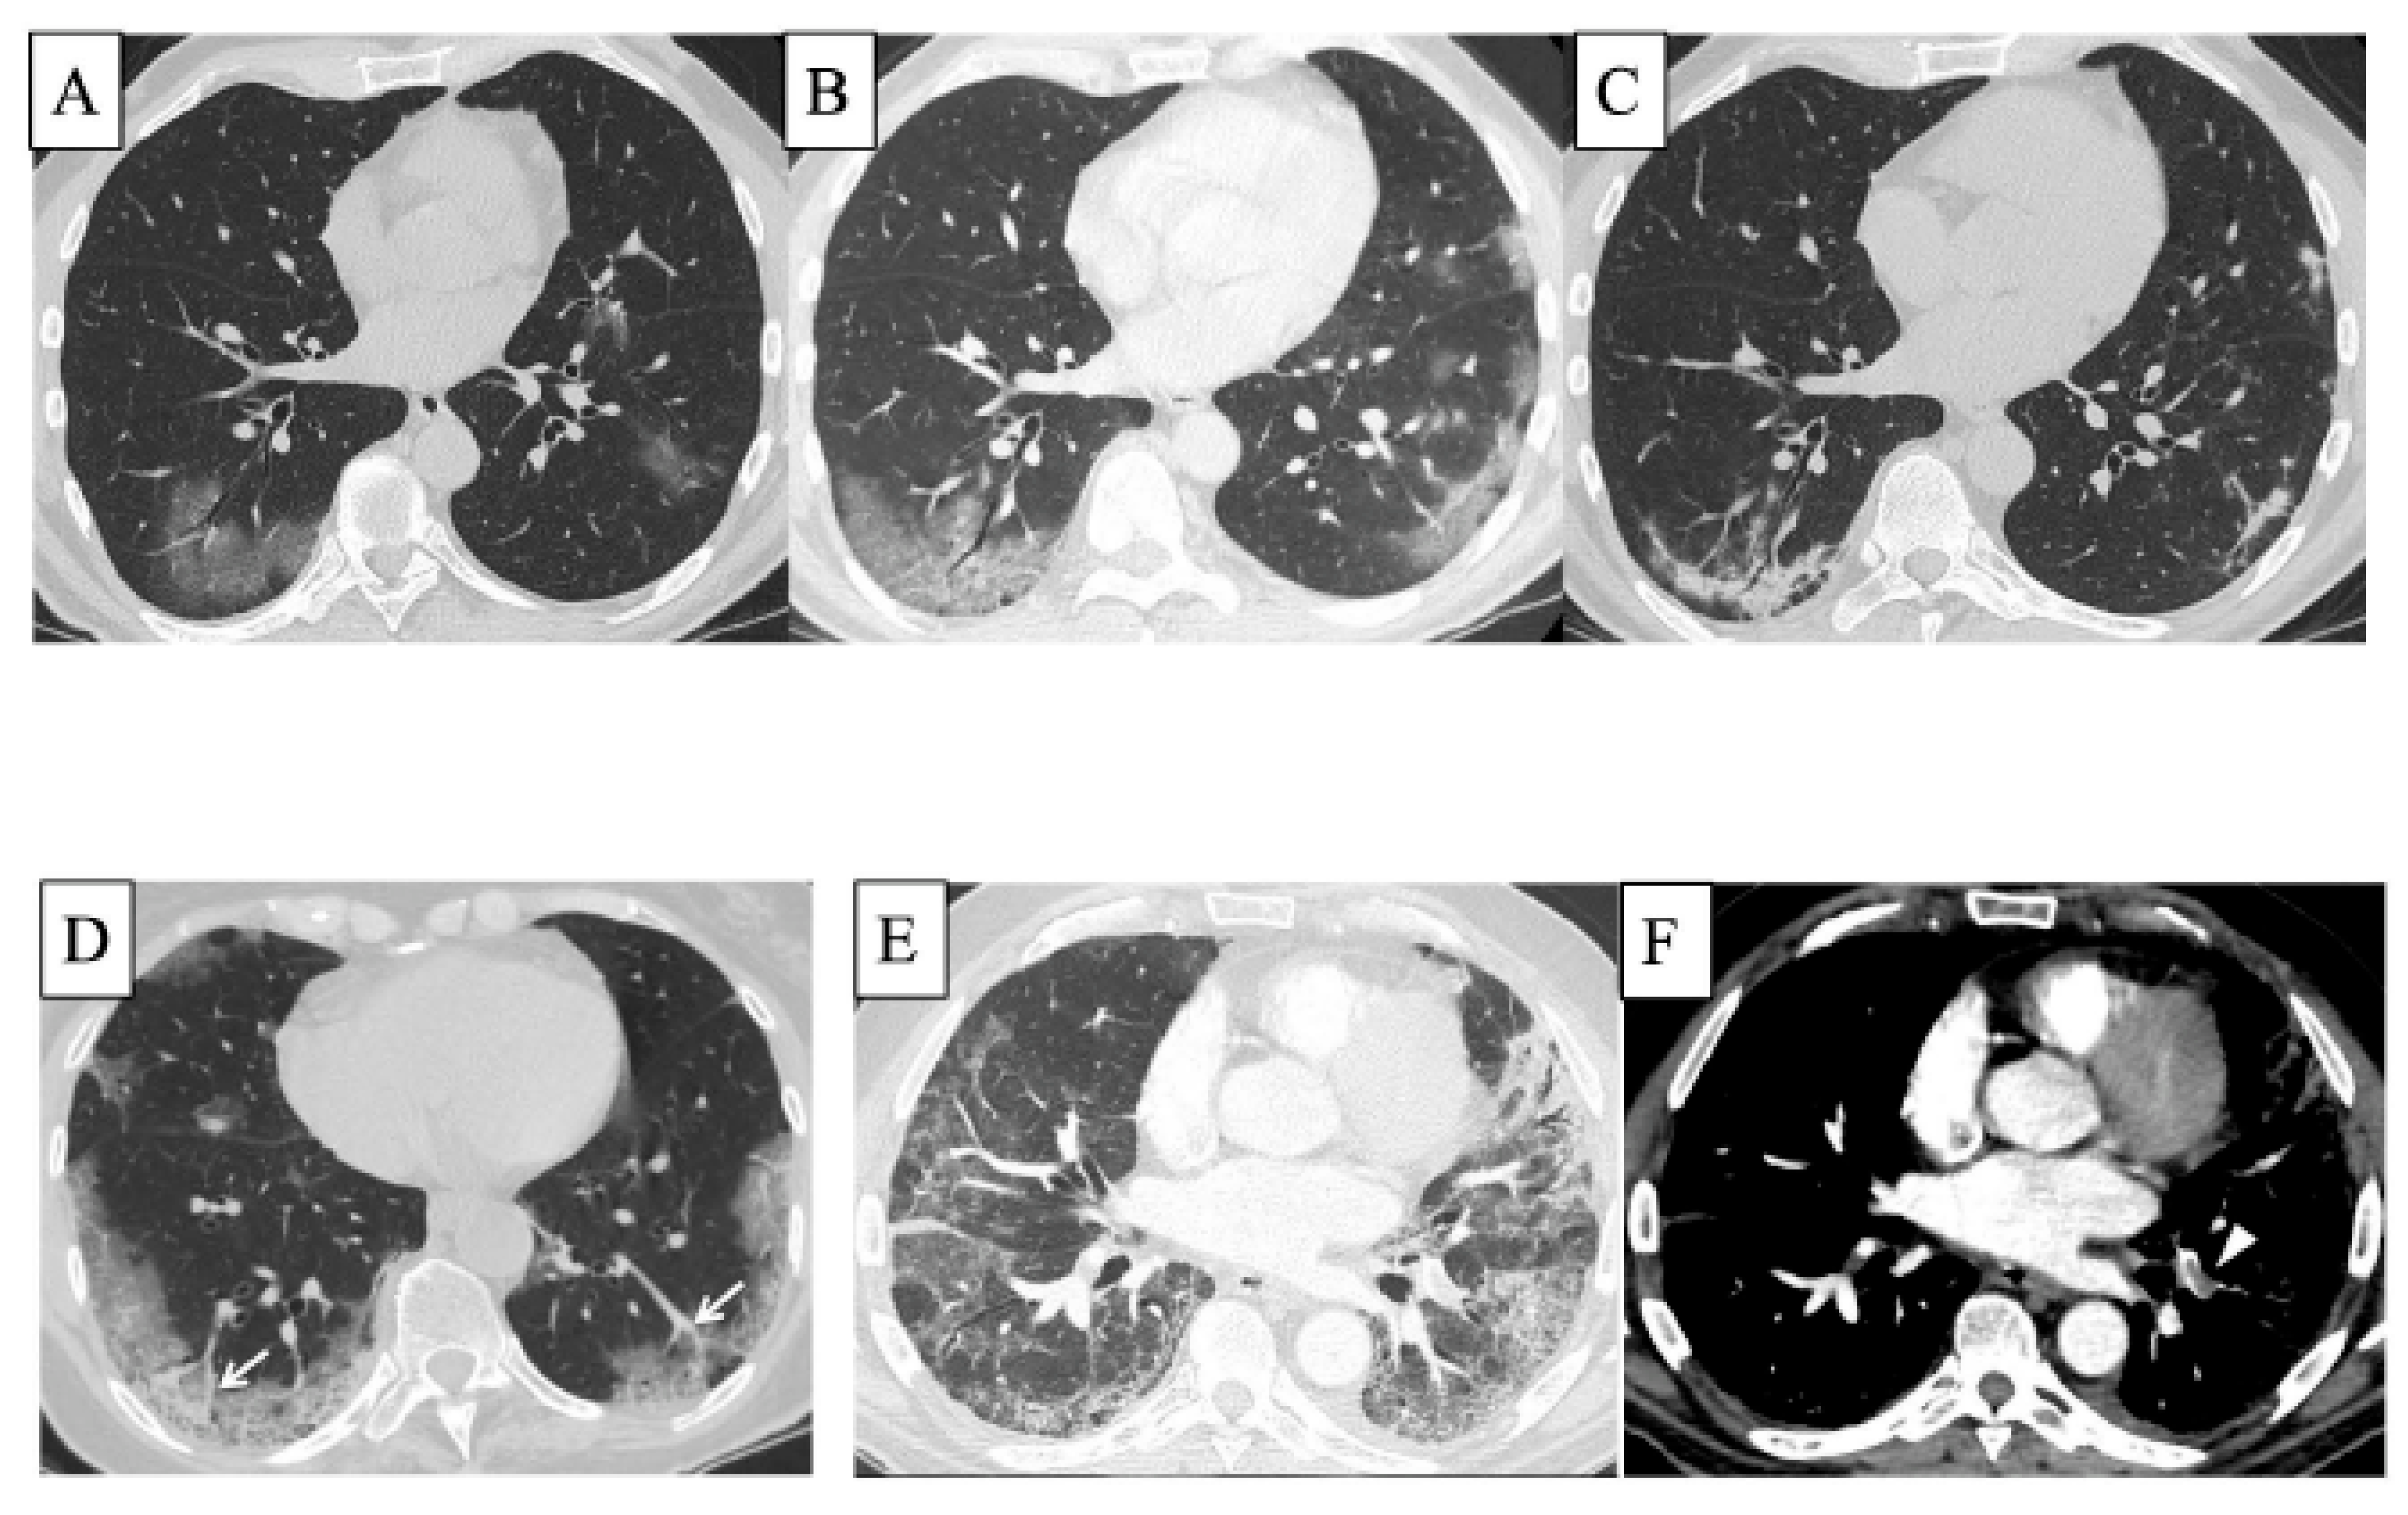

- Larici, A.R.; Cicchetti, G.; Marano, R.; Bonomo, L.; Storto, M.L. COVID-19 pneumonia: Current evidence of chest imaging features, evolution and prognosis. Chin. J. Acad. Radiol. 2021, 4, 229–240. [Google Scholar] [CrossRef] [PubMed]

- Iwasawa, T.; Sato, M.; Yamaya, T.; Sato, Y.; Uchida, Y.; Kitamura, H.; Hagiwara, E.; Komatsu, S.; Utsunomiya, D.; Ogura, T. Ultra-high-resolution computed tomography can demonstrate alveolar collapse in novel coronavirus (COVID-19) pneumonia. Jpn. J. Radiol. 2020, 38, 394–398. [Google Scholar] [CrossRef]

- Lang, M.; Som, A.; Carey, D.; Reid, N.; Mendoza, D.P.; Flores, E.J.; Li, M.D.; Shepard, J.O.; Little, B.P. Pulmonary Vascular Manifestations of COVID-19 Pneumonia. Radiol. Cardiothorac. Imaging 2020, 2, e200277. [Google Scholar] [CrossRef]